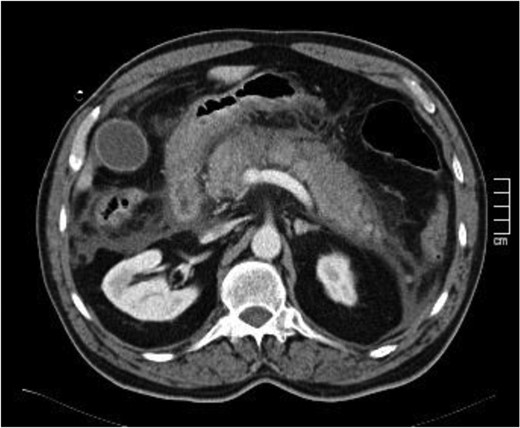

The case report refers to a 62-year-old man with medical history of hypertension, dyslipidemia and previous coronary stent placement. He went to the emergency department with upper abdominal pain with few hours of onset and vomits. The initial serum amylase was 2306 U/L and urinary amylase was 14 231 U/L. He met only one Ranson criteria at admission (Table 1). The first CT showed signs of a non-complicated acute pancreatitis (Fig. 1). He remained under surveillance and suffered clinical deterioration with progressive abdominal pain and tenderness and for this reason he was admitted on the intensive care unit (with an APACHE II score at admission of 15) where he progressed rapidly to multiple organ failure in <24 h. Due to this sudden worsening, with suspicion of a bowel perforation, a new CT scan was performed, showing significant gas dissection through the fascial planes with pneumoperitoneum and pneumoretroperitoneum (Fig. 2), however, without extraluminal contrast leakage evidence. This radiological gaseous pattern could not exclude a visceral perforation and raised the possibility of an anaerobe gas-producing bacteria presence. This sudden and progressive clinical deterioration together with an uncertain perforation or even an infected pancreatitis requiring for drainage motivated the beginning of empiric antibiotherapy with Meropenem and Metronidazol and an exploratory laparotomy on the operating room.

(After 16 h) Signs of necrotizing pancreatitis with pneumoperitoneum and pneumoretroperitoneum, pneumobilia and air on the main pancreatic duct.